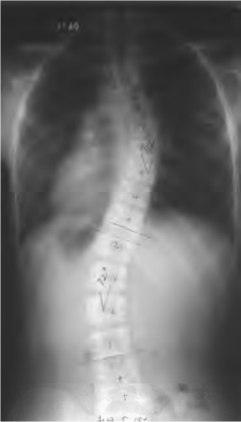

图2-3-7 KingⅣ型侧弯

全脊柱正位X线片示:侧弯弧度累及L4的长胸弯